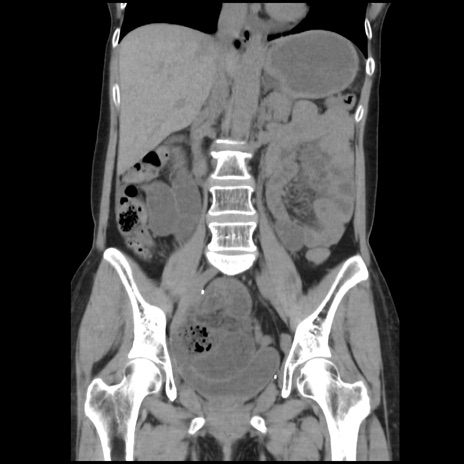

症例32(冠状断像)

【症例】40歳代 女性

【主訴】上腹部痛、嘔気・嘔吐

【現病歴】約9時間前頃から急に上腹部痛、嘔気、嘔吐が出現。改善しないため救急要請。

【既往歴】子宮頚癌(広汎子宮全摘術、放射線療法)、腸閉塞

【身体所見】腹部:平坦、軟、腸雑音亢進、上腹部を中心に腹部全体に圧痛あり。

【データ】WBC 8400、CRP 0.03